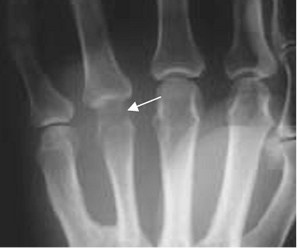

En las etapas subaguda y crónica, se produce erosión y destrucción ósea. Puede encontrarse también reacción perióstica en láminas. (16). (Fig 64 A, 64 B, 64 C y 64 D).

Fig 64 A. Artritis séptica.

Rx AP. Disminución del 4º espacio metacarpofalángico y pérdida en la nitidez de los contornos en la cabeza del metacarpiano, por artritis séptica.